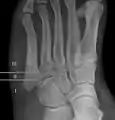

Diagnostic x-rays include anteroposterior, oblique, and lateral views and should be made with the foot in full flexion.

- Proximal diaphysis, typically stress fracture.[12][13]

- Metaphysis: Jones fracture[14]

-Tuberosity: Pseudo-Jones fracture[15] (avulsion fracture).[15]

Other proximal fifth metatarsal fractures exist, although they are not as severe as a Jones fracture. If the fracture enters the intermetatarsal joint, it is a Jones fracture. If, however, it enters the tarsometatarsal joint, then it is an avulsion fracture caused by pull from the peroneus brevis. An avulsion fracture is sometimes called a Pseudo-Jones fracture or a Dancer's fracture.

This injury should be differentiated from the developmental "apophysis" which is the secondary ossification center of the metatarsal bone. It is normally occurring at this site in adolescents. Differentiation is possible by characteristics such as absence of sclerosis of the fractured edges (in acute cases) and orientation of the lucent line: transverse (at 90 degrees) to the metatarsal axis for the fracture (due to avulsion pull by the peroneus brevis muscle inserting at the proximal tip) – and parallel to the metatarsal axis in the case of the apophysis.